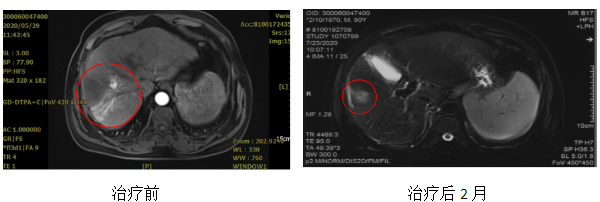

患者,男,50岁,原发性肝癌,分期:cT3bN0M0 IIIb期,Child-pugh分级:A级